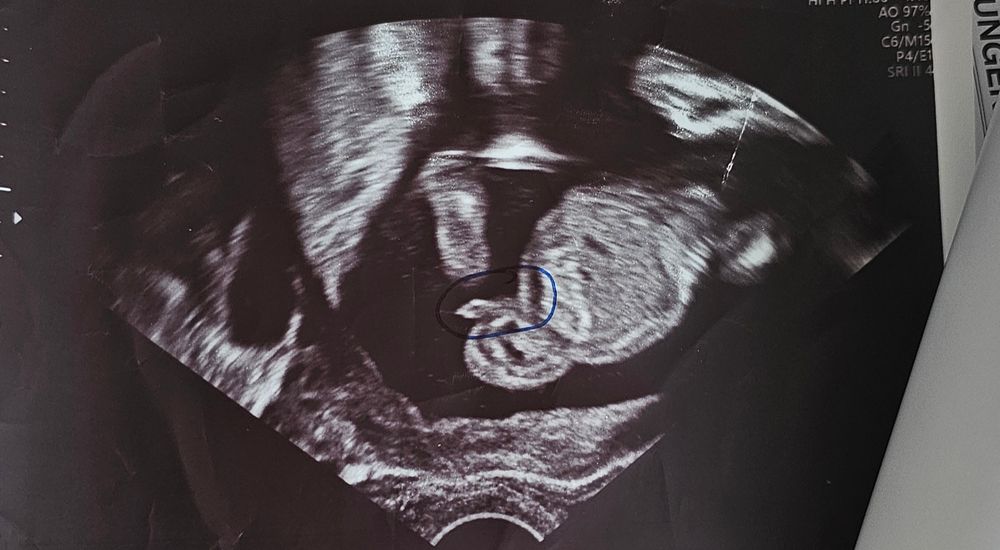

Если так гадать по половому бугорку, то он больше смахивает на девчачий, как и у меня. Но мне на 12 говорили девочка, на 15 сказали уже мальчик, так что не разберешь этих узи. Но этот метод полового бугорка не на все 100% верен. Можете даже посмотреть на этом сайте галерею http://www.ingender.com/Gender-Ultrasound/Gallery-Forum-Method.aspx?ID=2&;M=Nub&G=M

Помогите узнать пол Девочки, всем привет, сегодня была на УЗИ, у меня 14 неделек акушерских, врач сказал точно не может